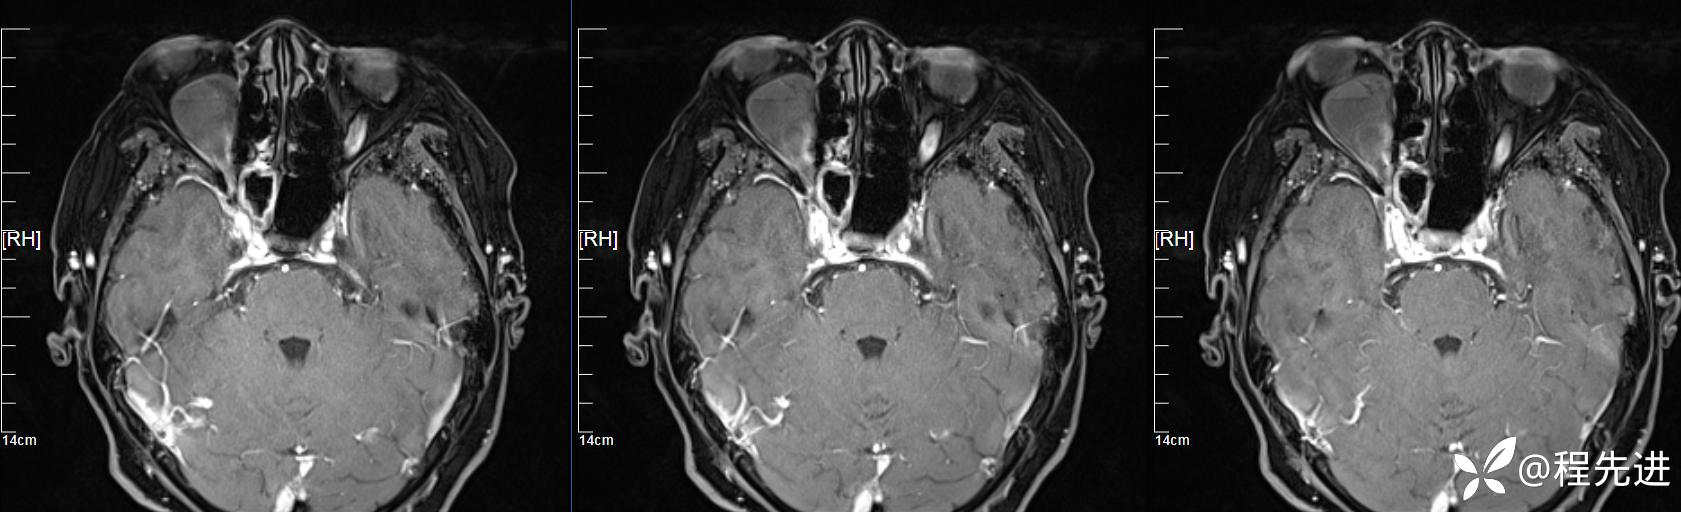

患者性别:女

患者年龄:64岁

简要病史:右眼突出10天

MR平扫+增强:

增强: